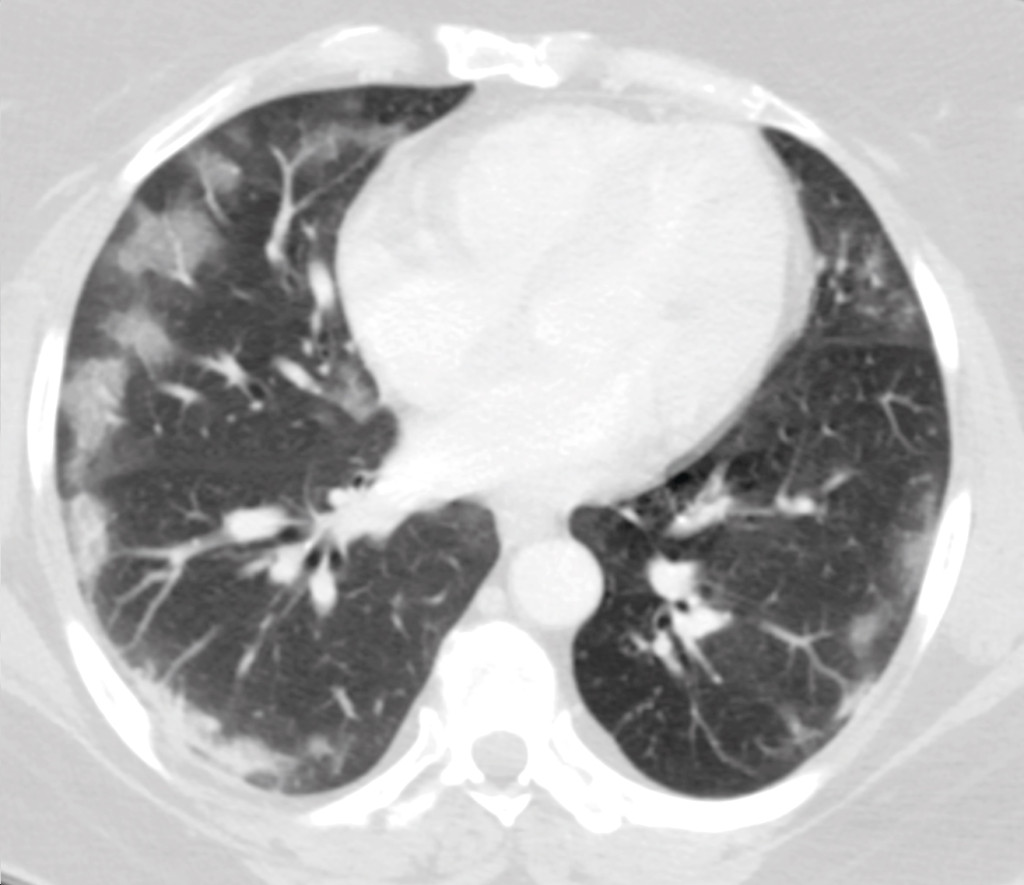

However, some patients with COVID-19 present with other symptoms. Over the past two weeks, our acute admissions unit has seen an additional five patients with similar symptoms, where COVID-19 has been confirmed by real-time PCR. The main complaint of all of these patients was abdominal pain, with some also having lower abdominal pain. In addition, they reported loss of appetite, nausea and vomiting. Some also had diarrhoea, but none had new symptoms from the respiratory tract. All underwent a CT examination of their abdomen, as part of the assessment of their abdominal pain, where the images showed typical findings for COVID-19 in the lungs (Figure 2).

Figure 2 CT image of patient (not actual case study) with acute abdomen as an early symptom. The image shows the lower part…

Figure 2 CT image of patient (not actual case study) with acute abdomen as an early symptom. The image shows the lower part of the thorax and shows patchy, bilateral characteristic ground glass opacity with peripheral distribution. The patient gave consent for the image to be published.